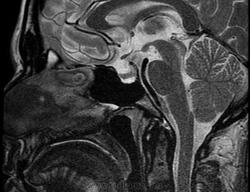

Ж, 37 лет. Наблюдается по поводу микроаденомы гипофиза, исследование в динамике. Предыдущие снимки сделаны в другом учреждении около года назад, картинка примерно такая же, однако на пленке отсроченные и постконтрастные снимки отсутствуют. В заключении была обозначена микроаденома округлой формы 3мм в диаметре.

Вот такая интересная картинка у нас получилась:

T2

Не полупустой, в нижних отделах странной формы аденома. Плоская какая-то. За аденому то, что она хоть и медленно, но накапливает контраст, который в ней задерживается после того, как уже почти полностью вымылся из здоровой паренхимы аденогипофиза. Полупустой гипофиз (вернее полупустое турецкое седло, ещё вернее вторично "пустое" турецкое седло) получается после удаления аденомы. Или после самопроизвольного опорожнения кисты/кистозной аденомы гипофиза. 2 часа назд такое контролировал.

Честно говоря, я сначала подумал, что гипофиз как будто "висит" над дном турецкого седла, а под ним - жидкость. После контрастирования действительно - аденома.

Нет, оказалось, что это вовсе не жидкость, а по характеру накопления парамагнетика - аденома необычной формы и локализации.